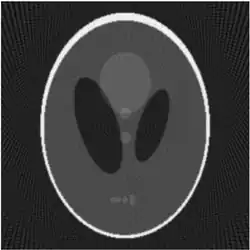

If a function represents an unknown density, then the Radon transform represents the projection data obtained as the output of a tomographic scan. The inverse of the Radon transform can be used to reconstruct the original density from the projection data, and thus it forms the mathematical underpinning for tomographic reconstruction, also known as iterative reconstruction.

Explicit and computationally efficient inversion formulas for the Radon transform and its dual are available. The Radon transform in dimensions can be inverted by the formula:[11] where , and the power of the Laplacian is defined as a pseudo-differential operator if necessary by the Fourier transform: For computational purposes, the power of the Laplacian is commuted with the dual transform to give:[12] where is the Hilbert transform with respect to the s variable. In two dimensions, the operator appears in image processing as a ramp filter.[13] One can prove directly from the Fourier slice theorem and change of variables for integration that for a compactly supported continuous function of two variables: Thus in an image processing context the original image can be recovered from the 'sinogram' data by applying a ramp filter (in the variable) and then back-projecting. As the filtering step can be performed efficiently (for example using digital signal processing techniques) and the back projection step is simply an accumulation of values in the pixels of the image, this results in a highly efficient, and hence widely used, algorithm.